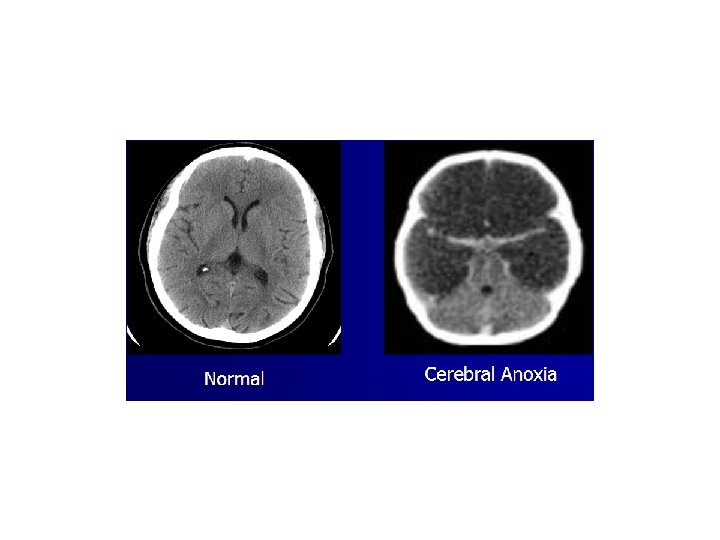

Causes of Brain Death • • • Cerebral anoxia Cerebral hemorrhage Subarachnoid hemorrhage Trauma Meningitis